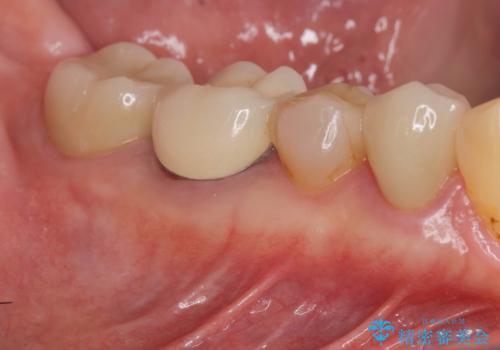

目立つゴールドをセラミックで白くしたい

- 笑った時に目立つゴールド修復を、白く自然なセラミック治療に置き換えたいとセラミック治療を希望され来院されました。

ゴールドの除去後に虫歯を丁寧に除去、セラミックにて自然な美しさを回復できるよう治療を計画します。